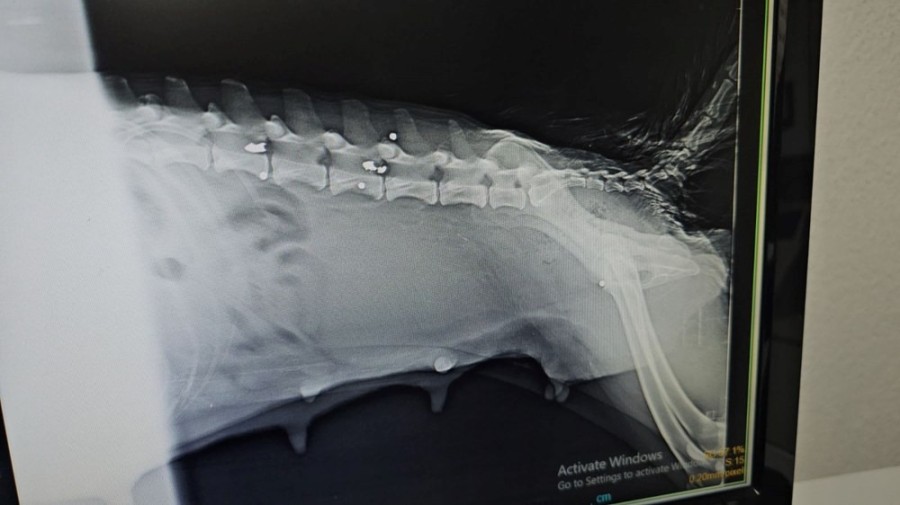

YAKIN MESAFEDEN ATEŞ EDİLMİŞ

Köpeğin yaralı, yavruların yeni doğmuş olarak geldiğini ifade eden Veteriner Hekim Ömer Faruk Alkan, "Röntgeni çekip muayene yaptıktan sonra yakın mesafeden ateş edildiğini, saçmaların omuriliğin içine ve vücuduna saplandığını gördük. Omuriliktekini arka tarafı felç kalacağı için saçmayı bulup çıkarttık. Omuriliğin etrafındaki kemik dokusunu serbestleştirerek oradaki sinirin baskısından kurtardık. Sonra yavrularının yanına koyduk." dedi.